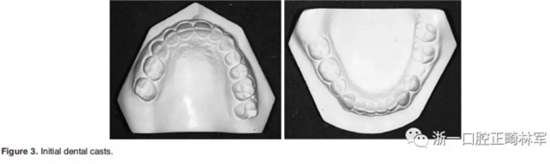

2.主訴:左下乳磨牙滯留、微笑不美觀

3.體格檢查:直面型,露齦笑,深覆合、合平面傾斜(Figure 1)。上中線偏右3mm,下中線偏左2mm。磨牙II類關(guān)系,左側(cè)尖牙II類關(guān)系,右側(cè)尖牙I類關(guān)系,左下第二磨牙低位咬合,右上前磨牙缺失。覆蓋率為100%,覆蓋度為4mm。咬合平面重度傾斜,左側(cè)向下移位(Figure 2、3)。